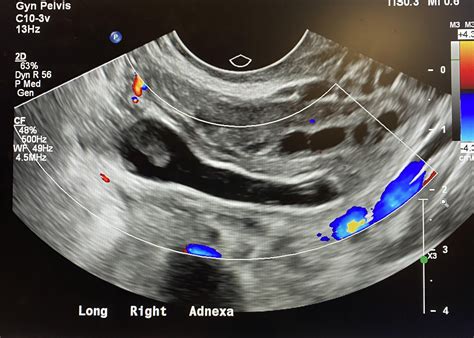

• Hyperemia: Increased blood flow to the appendix, which can be detected using Doppler ultrasound, is another sign of inflammation.

• Image Acquisition: The radiologist moves the probe to capture images of the appendix from different angles. Doppler ultrasound may be used to assess blood flow.